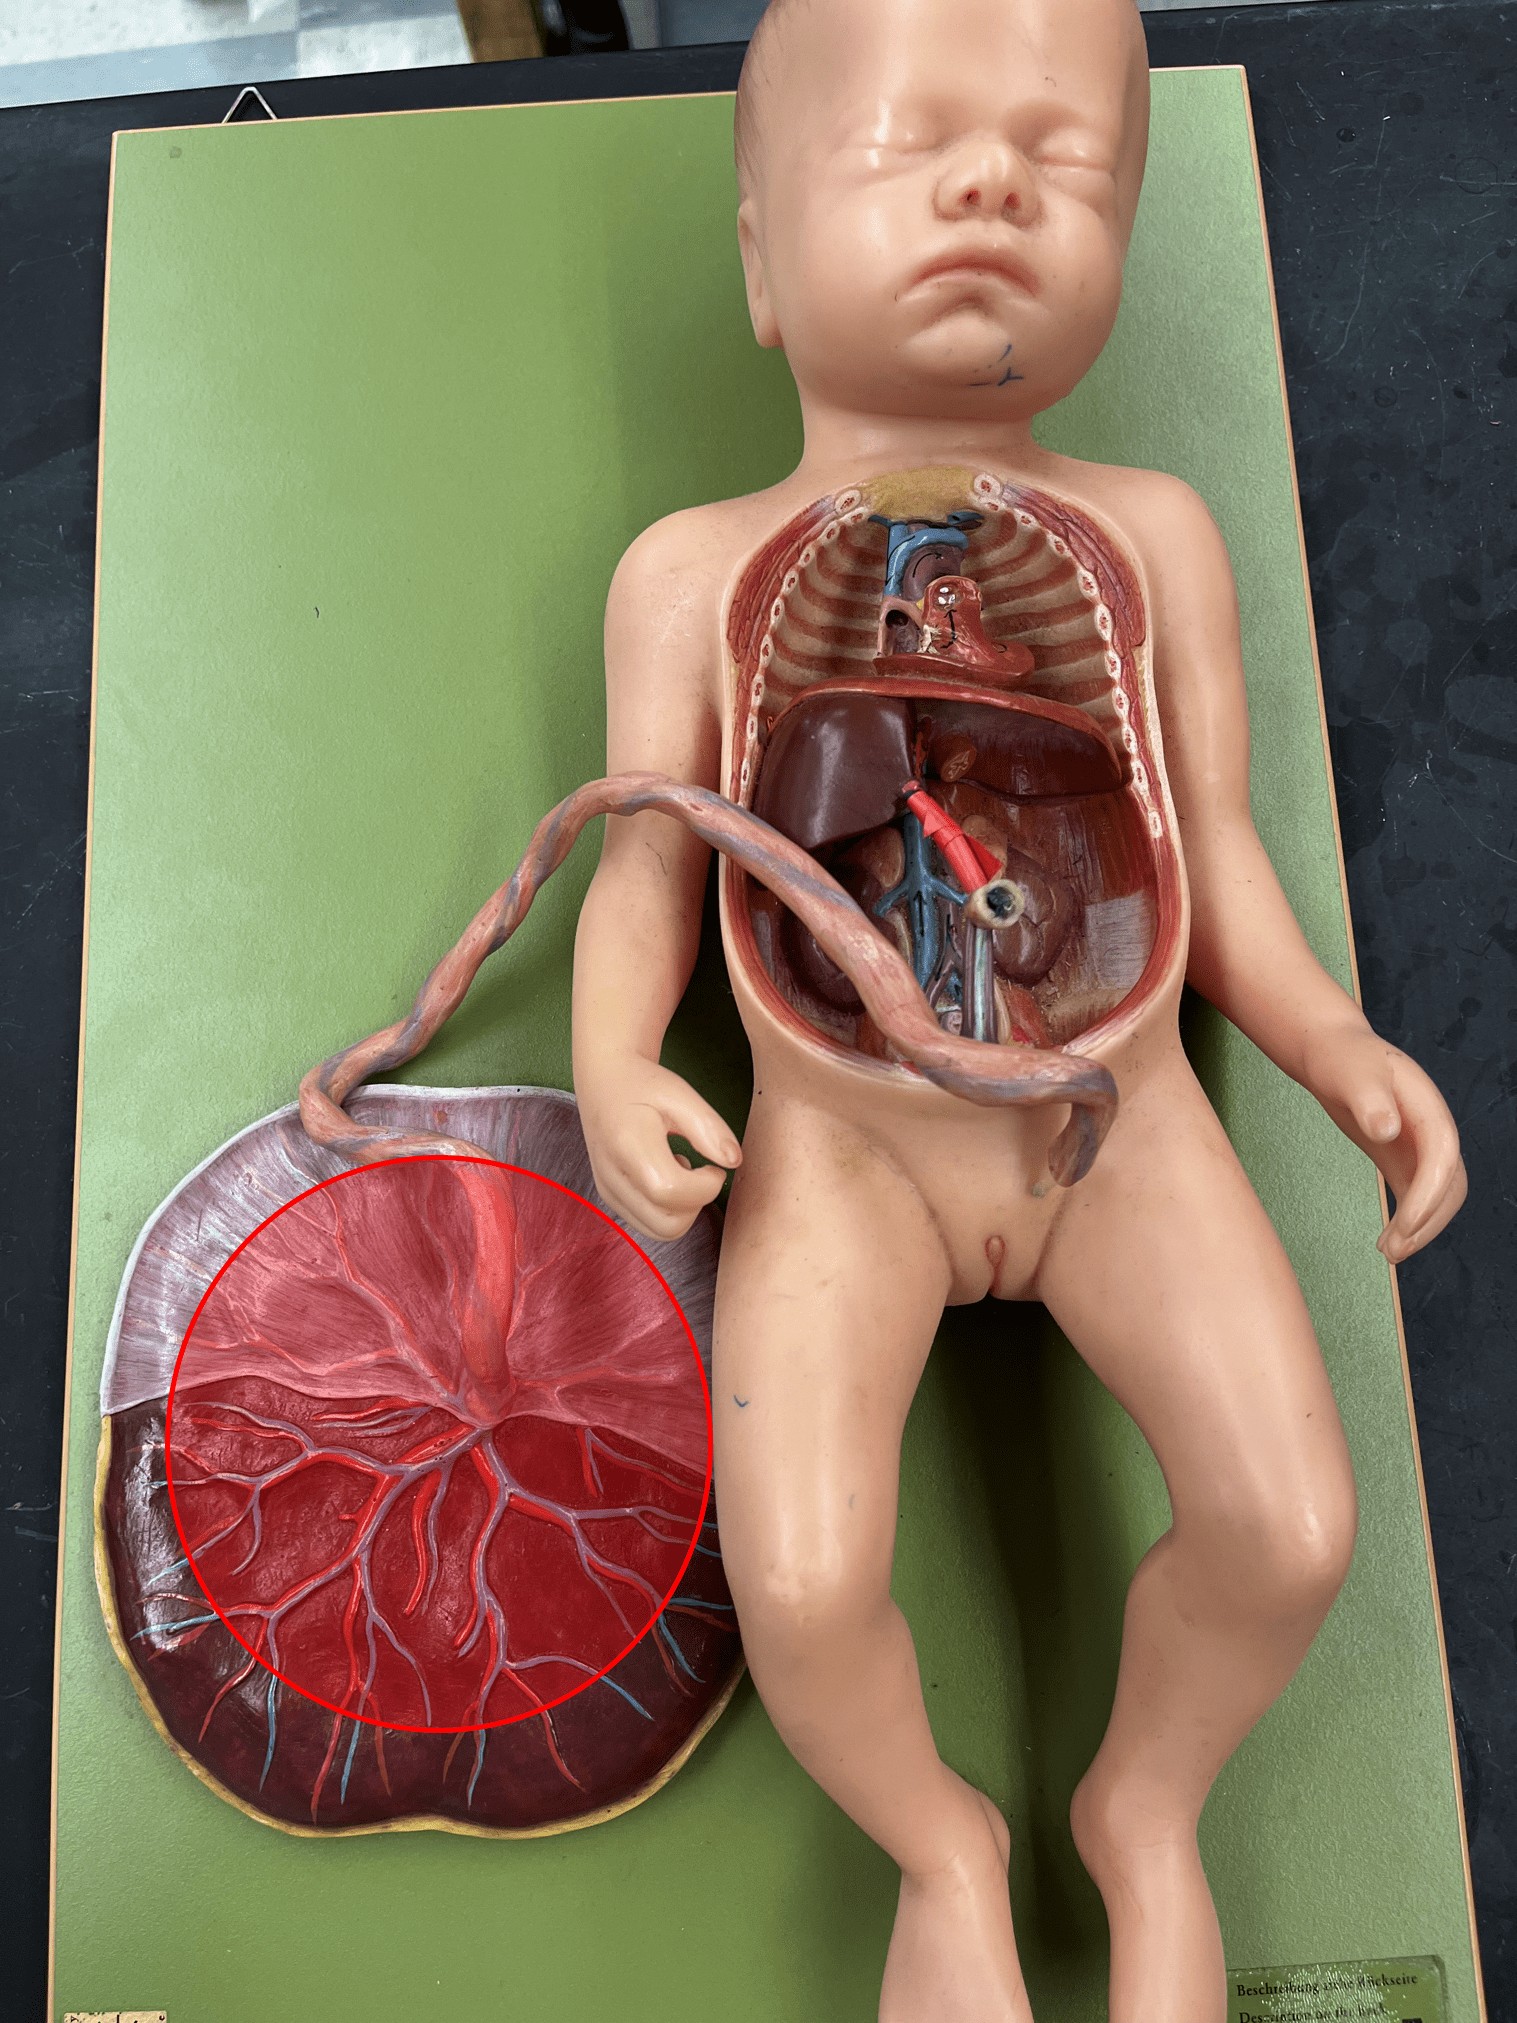

14

New cards